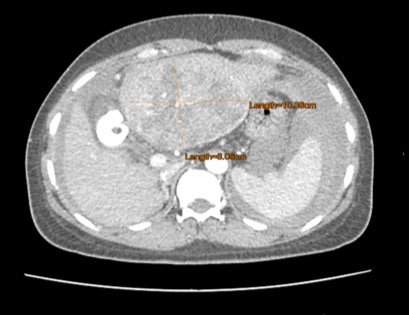

ภาพเอกซเรย์คอมพิวเตอร์ ของผู้ป่วยมะเร็งในตับกลีบซ้ายกลางลำตัวขนาดใหญ่ 10.4 ซม. มารพ. เพราะก้อนแตก เลือดออกในช่องท้องปริมาณมาก มีอาการเสียเลือดและความดันเลือดตก